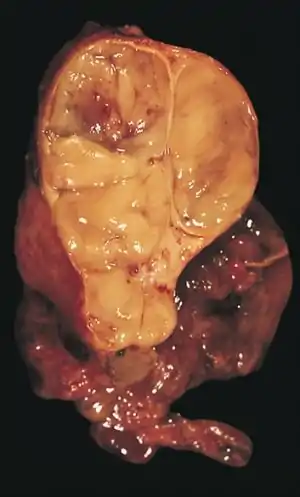

The diagnosis is made via histologic examination by a pathologist, after obtaining a tissue sample of the mass. Final tumor classification and staging is accomplished pathologically after formal surgical removal of the thymic tumor.

An encapsulated cystic thymoma.

A locally invasive circumscribed thymoma (mixed lymphocytic and epithelial, mixed polygonal and spindle).